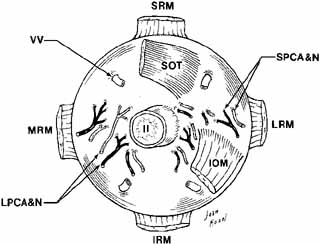

levator aponeurosis recession.43 The Globe The globe is located in the anterior orbit situated slightly superiorly

and laterally. The superior, medial, and inferior orbital rims extend

anteriorly to be on about the same frontal plane as the front of the

eye. The lateral rim is recessed 12 to 18 mm behind the cornea as measured

by exophthalmometry. Attached to the eye are the six extraocular

muscles, the optic nerve, the long and short posterior ciliary nerves, the

anterior and posterior ciliary arteries, and the vortex veins (Fig. 17). The globe is covered behind the corneal limbus by Tenon's

fascia and is supported in the orbit by Lockwood's ligament. The

average volume of the eye is about 6.5 cc compared to the orbital volume, which

is about 29.7 cc.2 The shape is not truly spheric; rather it is formed by the union of two

spheres, being that of the cornea and the sclera, with radius of curvatures

equal to 8 and 12 mm, respectively.  Fig. 17 Posterior view of the right globe after enucleation. (SRM, superior rectus muscle; VV, vortex veins; SOT, superior oblique tendon; II, cranial nerve II; LRM, lateral rectus muscle; SPCA & N, short posterior ciliary artery and nerve; LPCA & N, long posterior ciliary artery and nerve; MRM, medial rectus muscle; IRM, inferior rectus muscle; IOM, inferior oblique muscle) Fig. 17 Posterior view of the right globe after enucleation. (SRM, superior rectus muscle; VV, vortex veins; SOT, superior oblique tendon; II, cranial nerve II; LRM, lateral rectus muscle; SPCA & N, short posterior ciliary artery and nerve; LPCA & N, long posterior ciliary artery and nerve; MRM, medial rectus muscle; IRM, inferior rectus muscle; IOM, inferior oblique muscle)

|